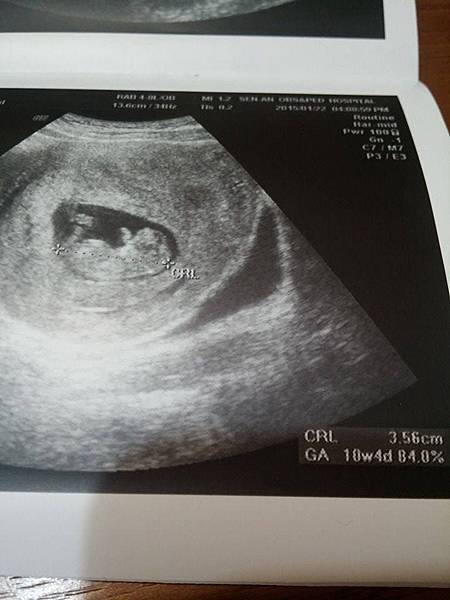

【2015.1.22~第四次產檢10W4D】~Dr.許

小bébé長到3.56公分,超音波攝影有看到手腳 (疑似雞雞??哈)

還跳動了一下,把媽媽笑到,回家趕快跟把拔講,

感覺小bebe是個男生耶~有這種預感,